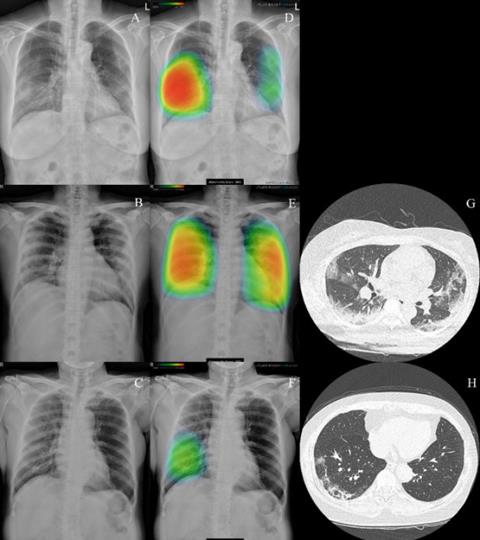

루닛 인사이트 CXR를 활용해 코로나19 폐렴이 표시된 흉부 엑스레이

루닛 인사이트 CXR을 활용해 279명의 흉부 엑스레이를 판독한 결과, AI는 약 95% 정확도로 코로나19를 검출해냈다. 영상의학과 전문의 판독 정확도가 약 91%라는 점을 고려할 때 상당히 높은 수치다.